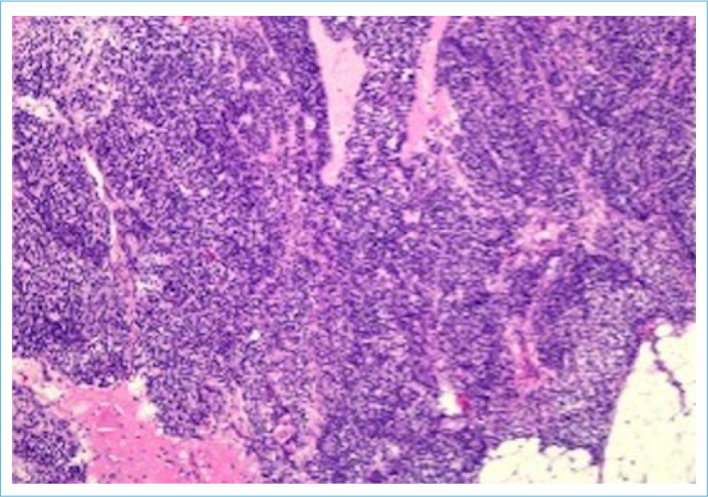

This is a case report of a 19-year-old nulligravid patient with a choroid plexus papilloma tumor in a mature cystic teratoma in the right adnexal area. The patient, who had abdominal pain and dyspepsia, showed a 9 cm diameter mass with a solid/cystic component, initially interpreted as a dermoid cyst in the right adnexal region. Mature cystic teratoma is a benign germ cell tumor and is common in women during the reproductive period. However, choroid plexus papilloma is a rare brain tumor. The diagnosis of ovarian choroid plexus papilloma can be made with imaging tests such as magnetic resonance imaging or computed tomography, and treatment is usually by surgical removal. Only four cases of ovarian teratoma with choroid plexus papilloma have been informed in the English literature, and this issue is the fifth.